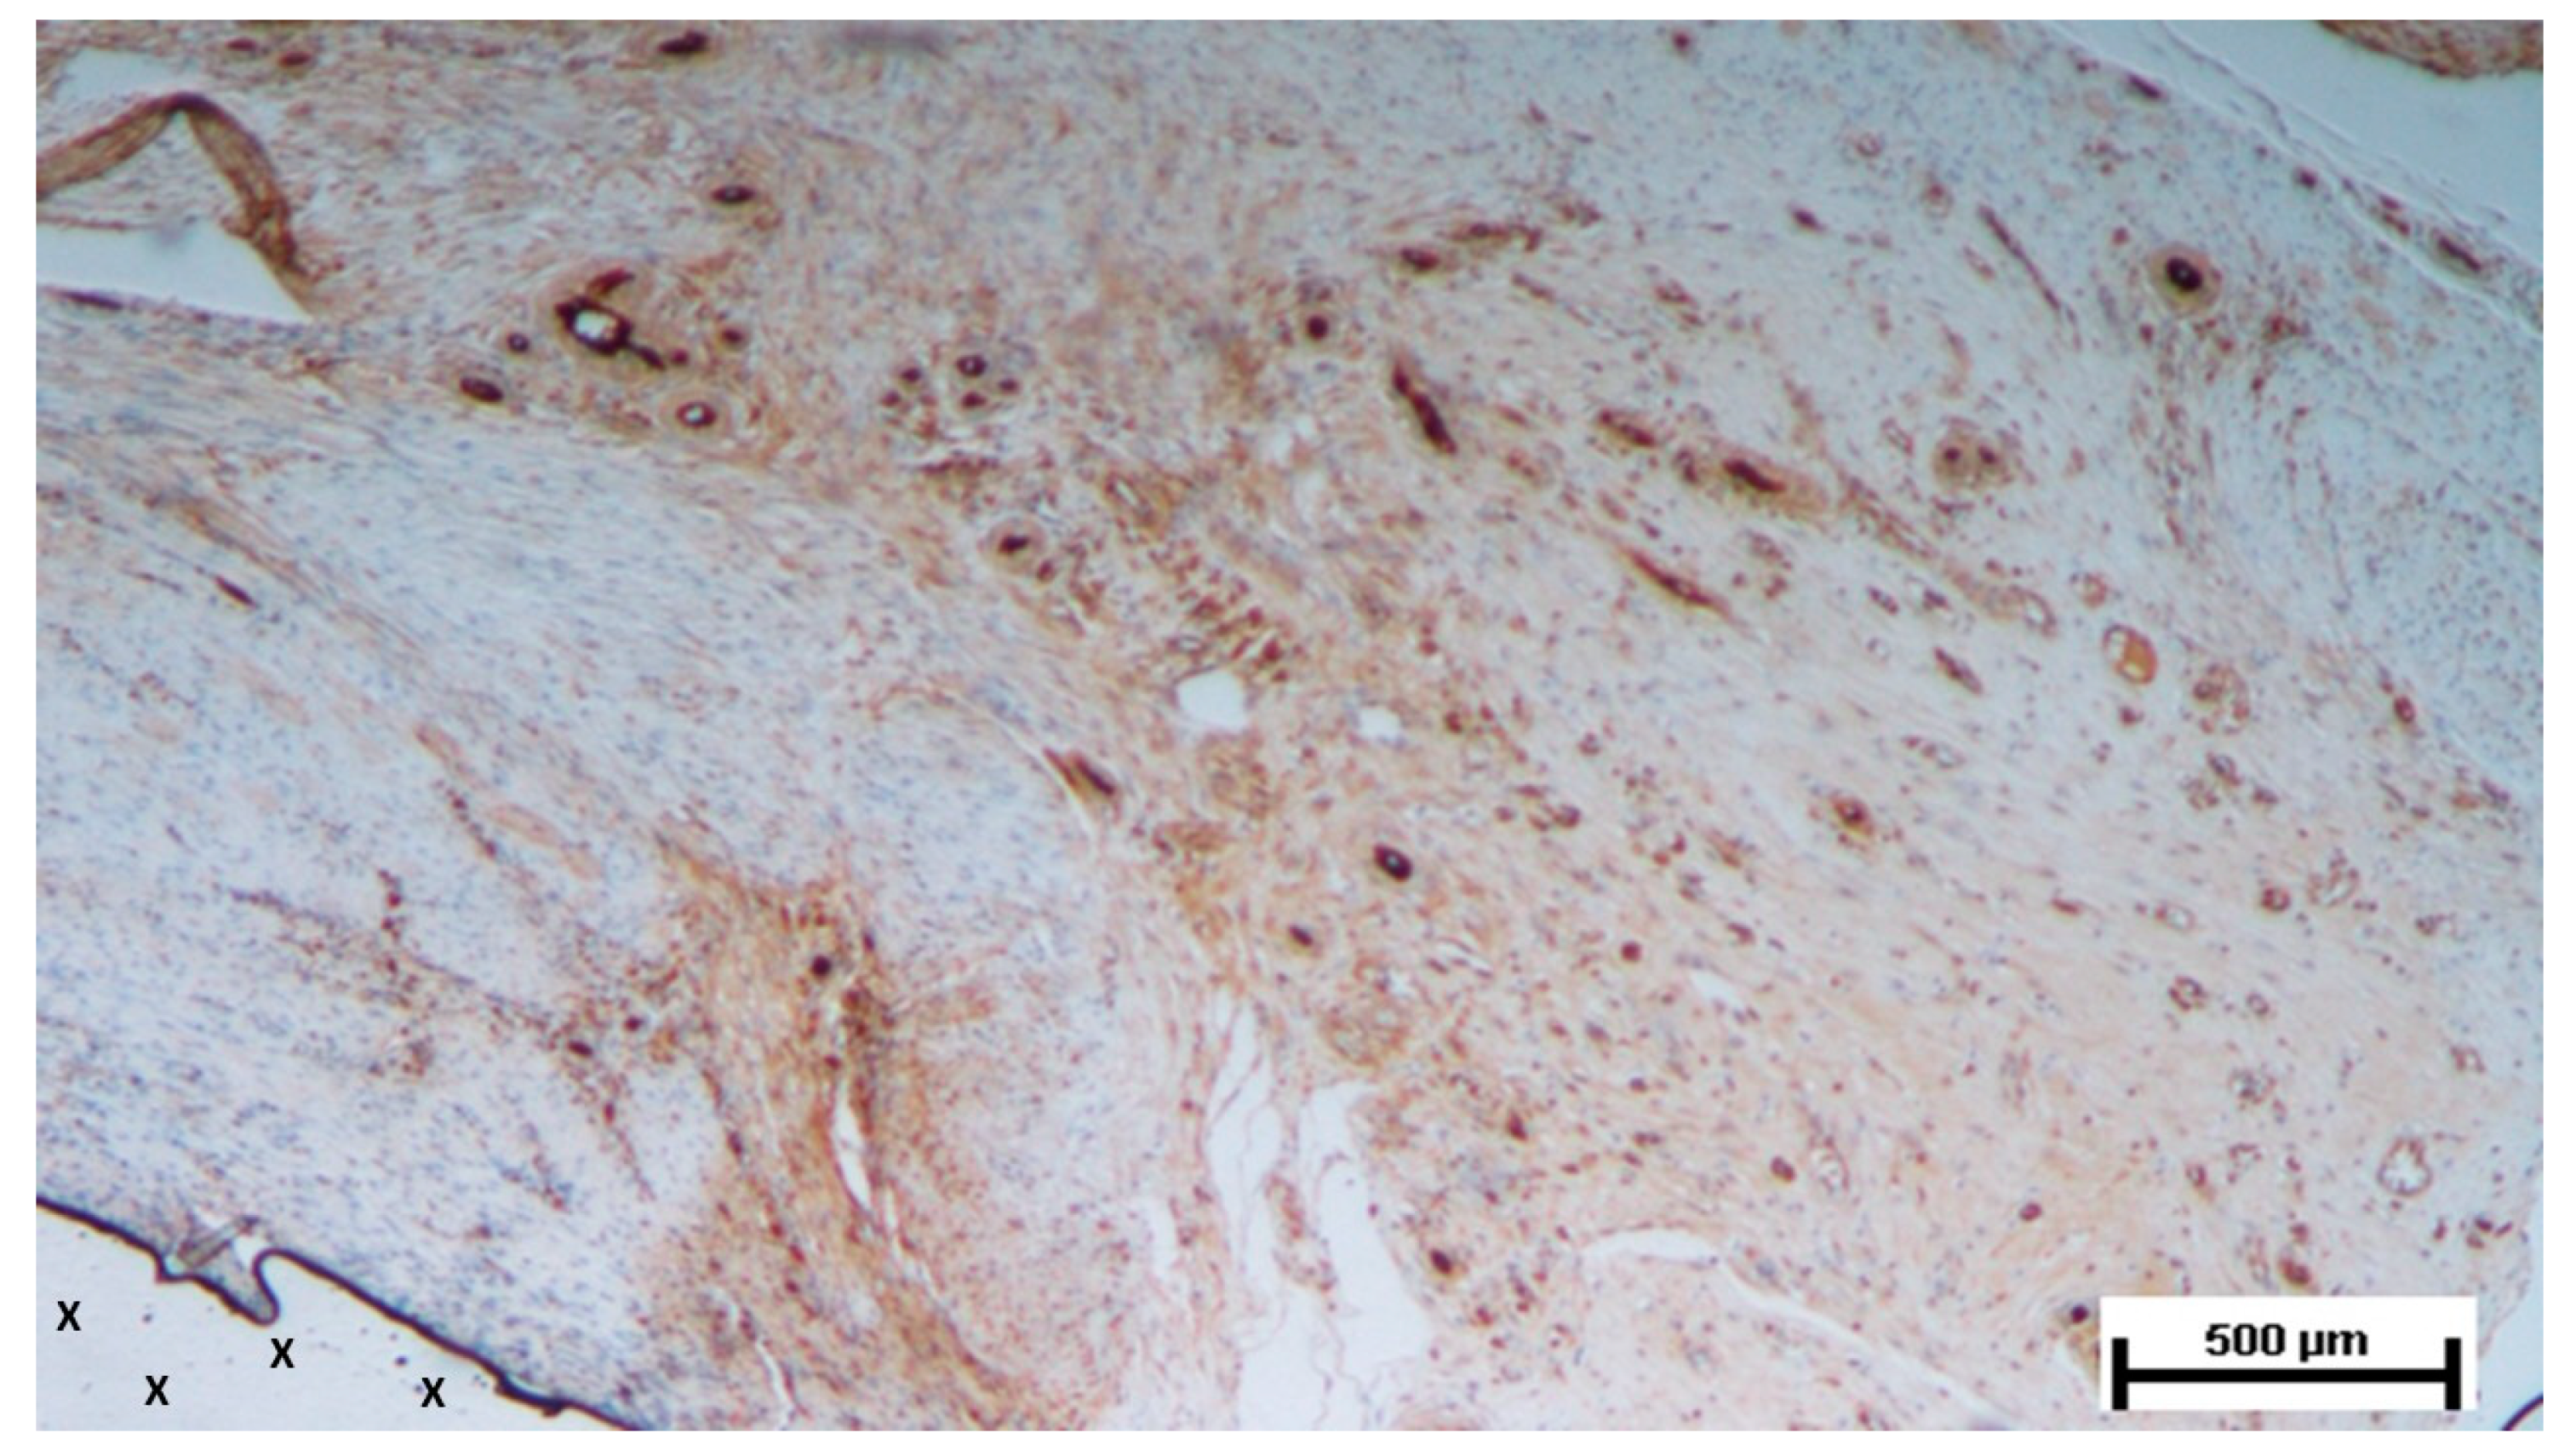

Figure 10. Biopsy taken four months post-implantation from the 3D scaffold of the S&S Hernia System. Numerous vascular elements in advanced stage of development (stained in brown), close to the S&S fabric (X). CD31 50X.

6-8 months post-implantation (long-term stage), there was a complete absence of inflammation, and the newly formed arteries and veins demonstrated full structural maturation across all components (Figure 11, Figure 12, Figure 13, Figure 14 & Figure 15).